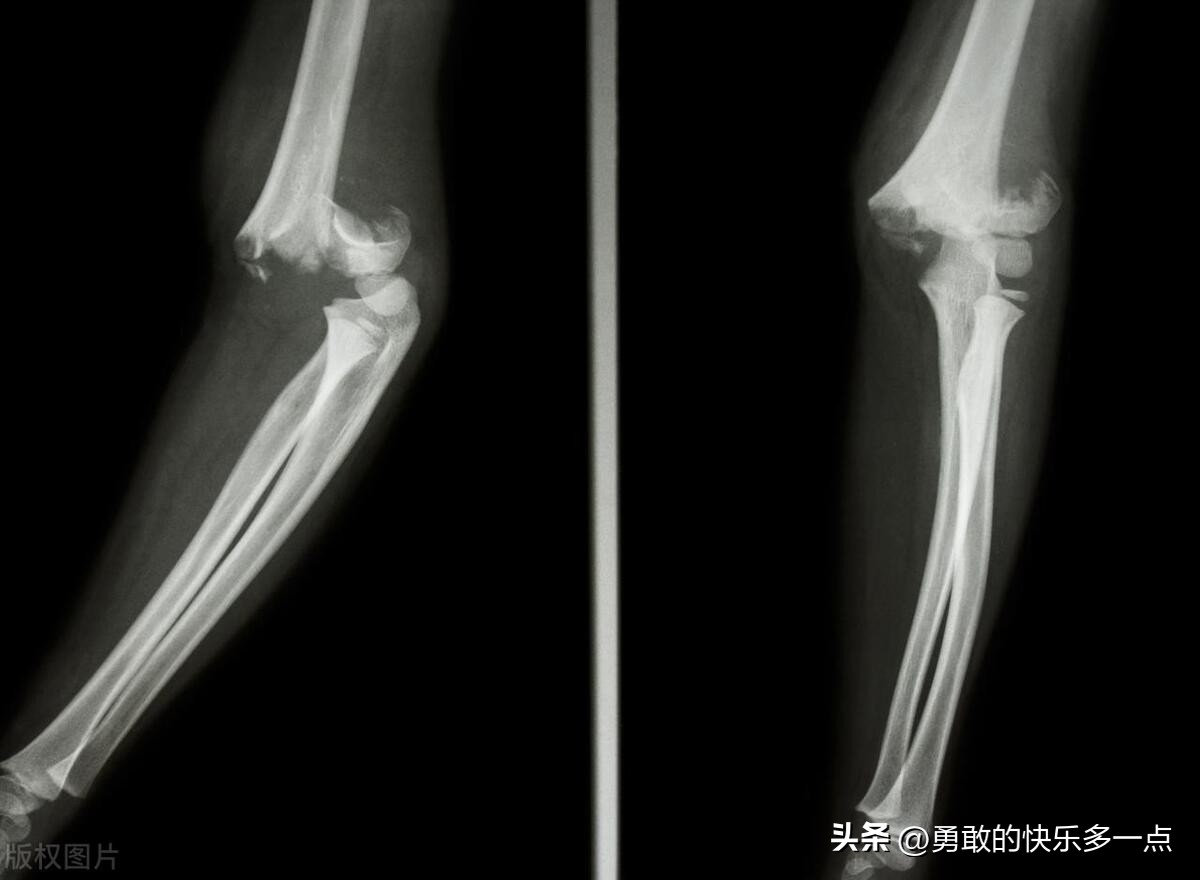

儿童外伤手部着地,肘部出现疼痛,肿胀,皮下瘀斑,肘部向后突出并处于屈曲位,这个时候就需要考虑是出现肱骨髁上骨折可能,及时需要拍片等专业检查,还需要特别注意是否合并神经血管损伤。(如下图)

典型的肱骨髁上骨折体征